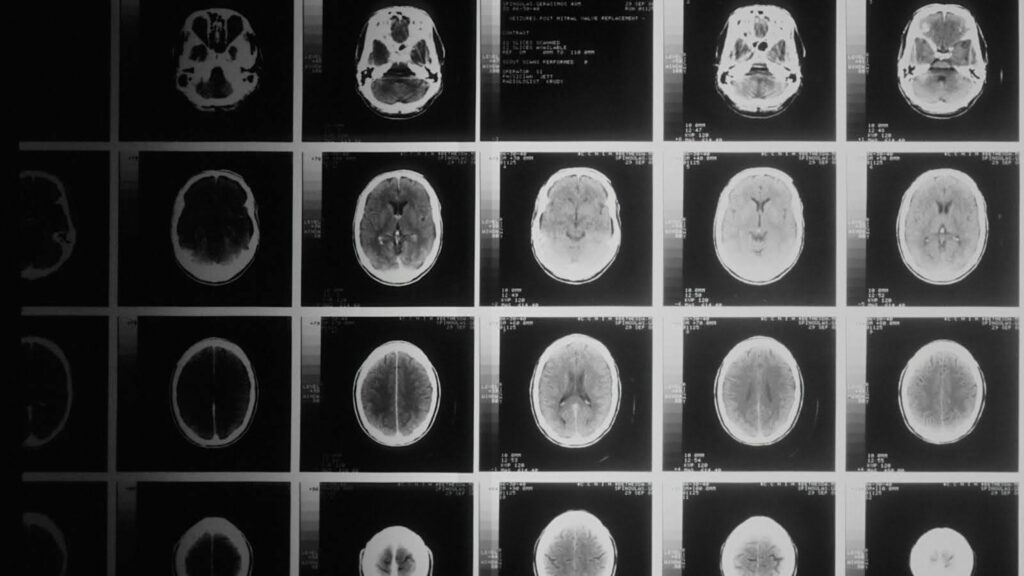

• AI 将脑部 MRI 转化为潜在的中风预测因子

AI 将脑部 MRI 转化为潜在的中风预测因子

研究人员使用 AI 分析常规脑部扫描,发现了一种前景良好的新方法,可以可靠地识别常见但难以检测的多中风先兆。在《Cerebrovascular Diseases》期刊上发表的一项研究中,来自Royal Melbour